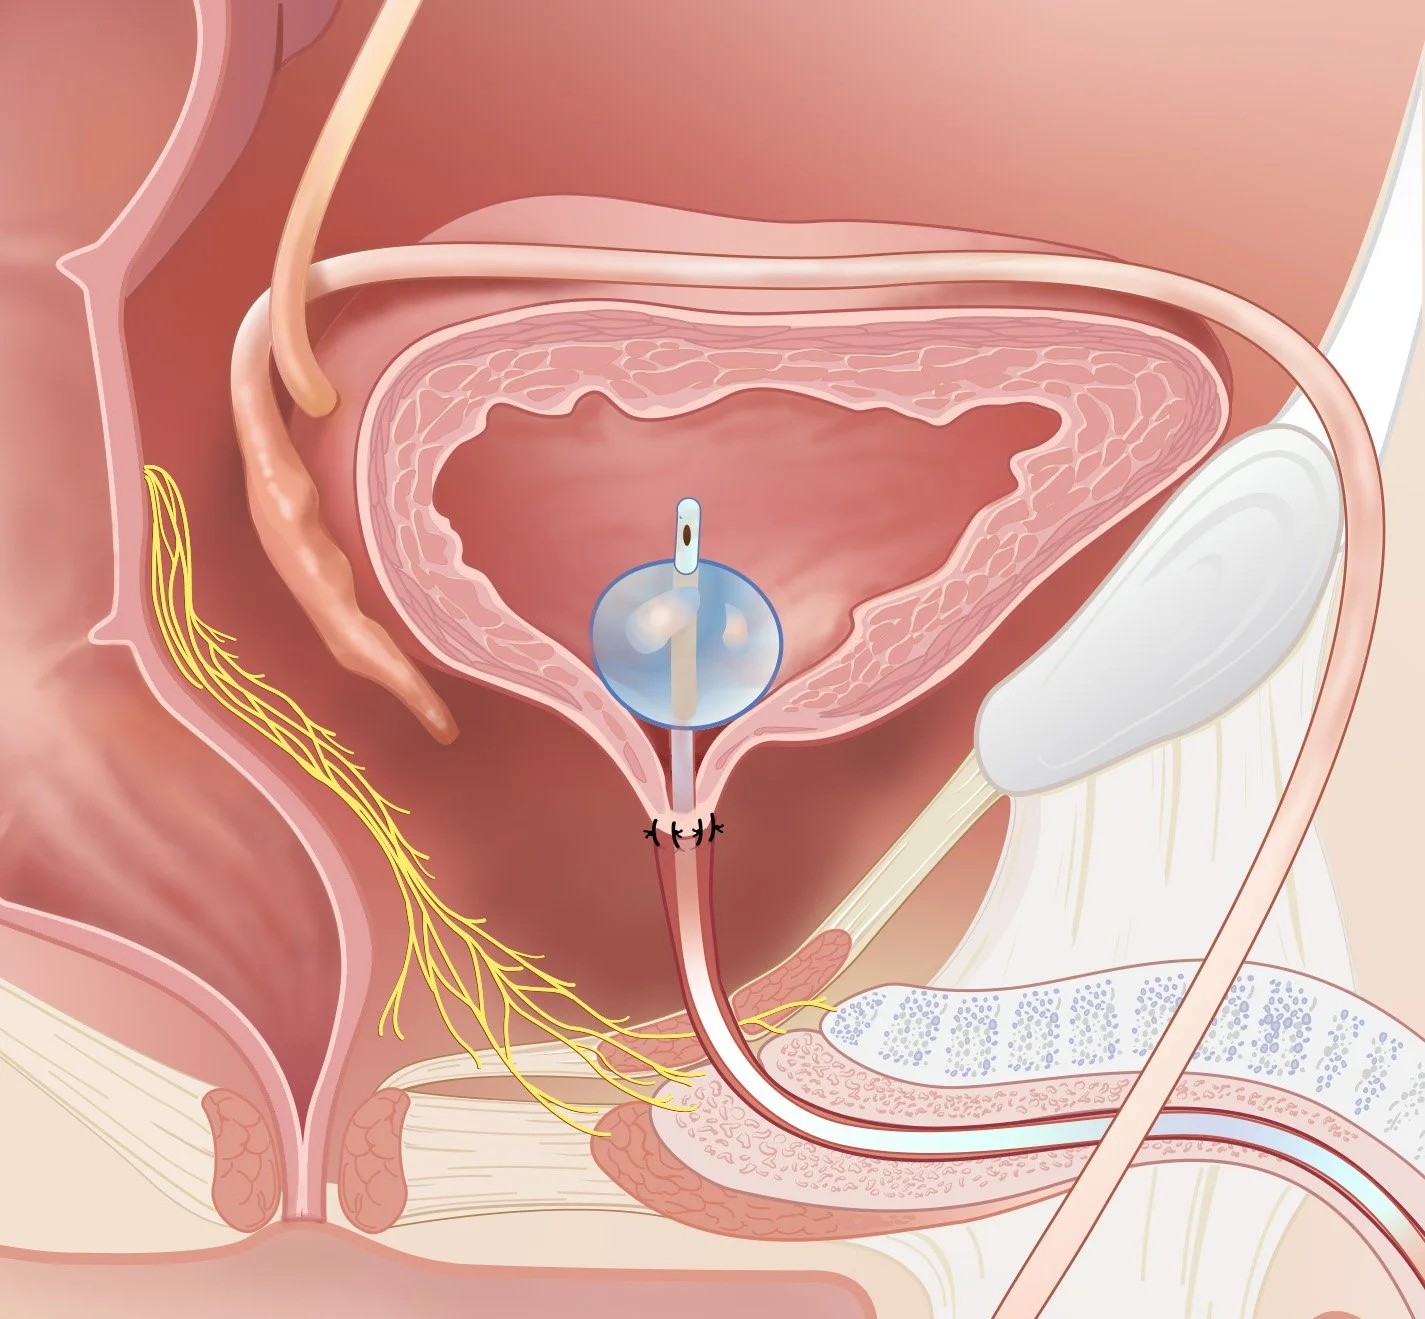

Surgical illustrations visually depict operative techniques, surgical anatomy, and complex procedures. They are created with high anatomical accuracy and serve as a visual bridge between complex surgical knowledge and learners, clinicians, or patients.

Prostate Cancer Booklet

Created clear, accurate, and visually engaging medical illustrations for a patient education booklet on prostate cancer for a hospital system. The illustrations simplified complex anatomical and clinical concepts, helping patients better understand diagnosis, treatment options, and disease progression.

Client: Northwell Hospital System

Patient Education: Prostate Cancer